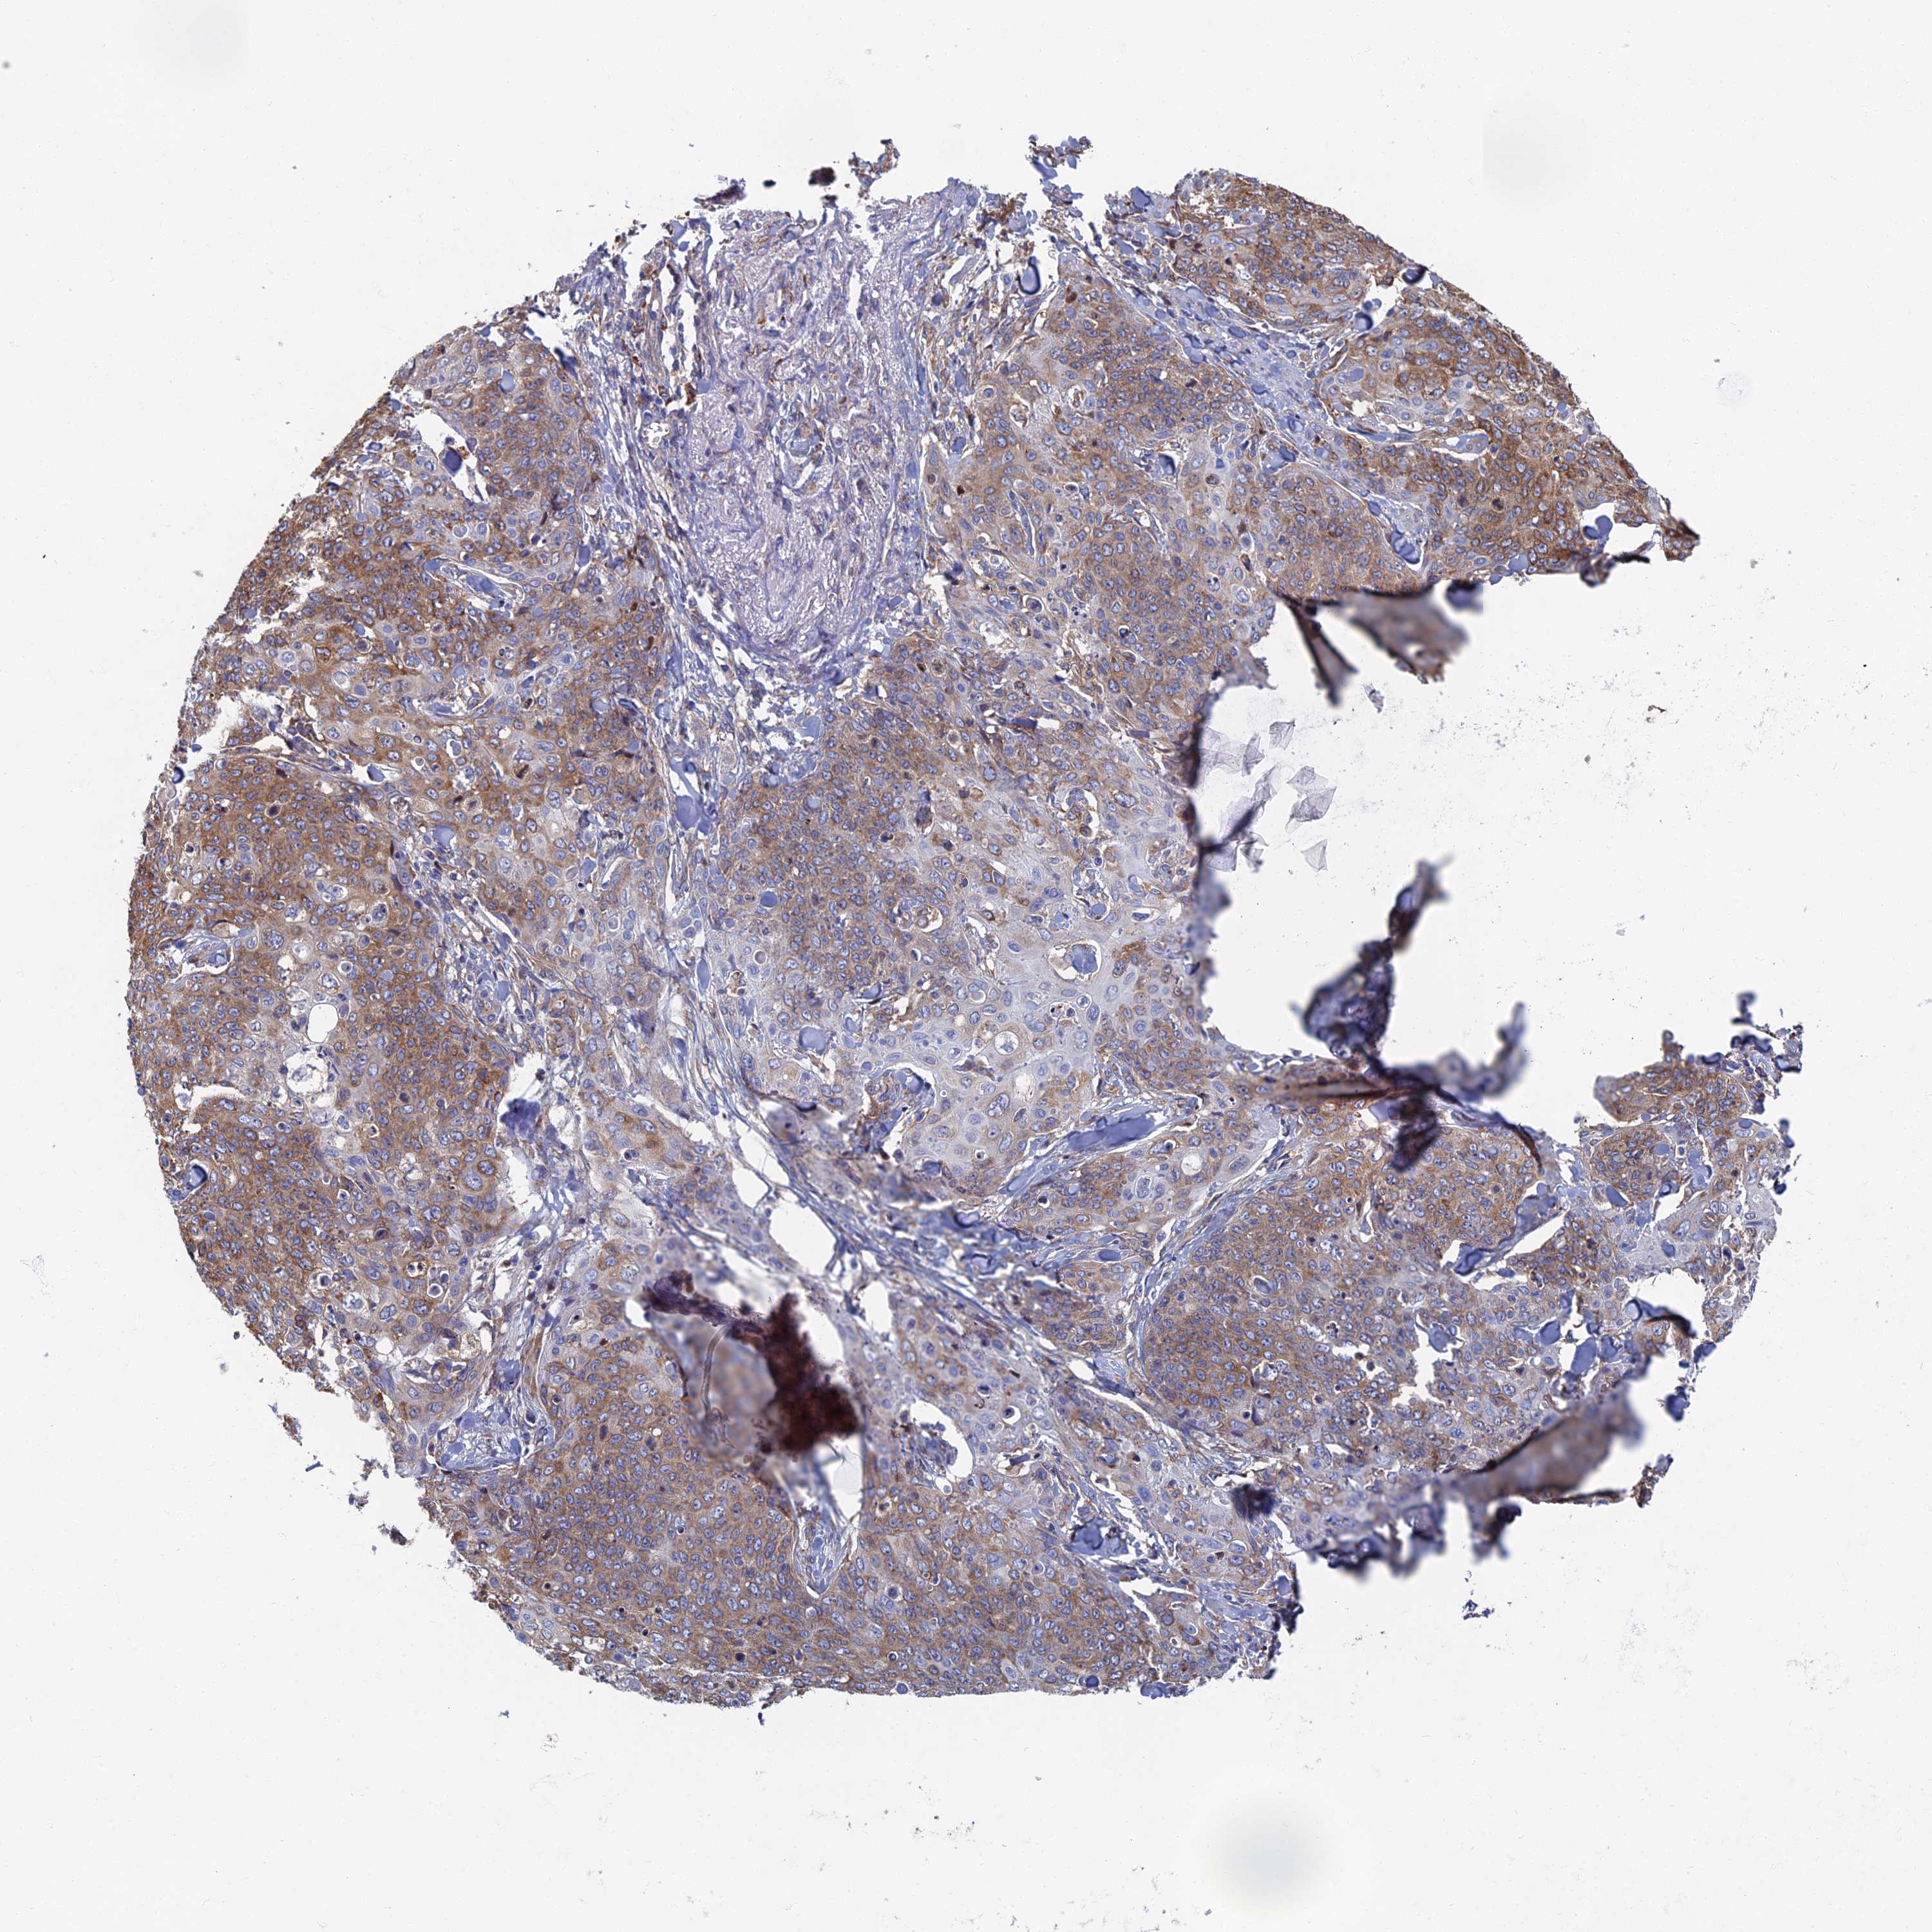

SKIN CANCER - Protein expressioni

A mouse-over function shows sample information and annotation data. Click on an image to view it in a full screen mode. Samples can be filtered based on level of antibody staining by selecting one or several of the following categories: high, medium, low and not detected. The assay and annotation is described here.

Antibody stainingi

Antibody staining in the annotated cell types in the current human tissue is reported as not detected, low, medium, or high, based on conventional immunohistochemistry profiling in selected tissues. This score is based on the combination of the staining intensity and fraction of stained cells.

Each image is clickable and will lead to virtual microscopy that enables deeper exploration of all samples and also displays staining intensity scores, fraction scores and subcellular localization as well as patient and tissue information for each sample.

Antibody HPA057159

Squamous cell carcinoma, NOS